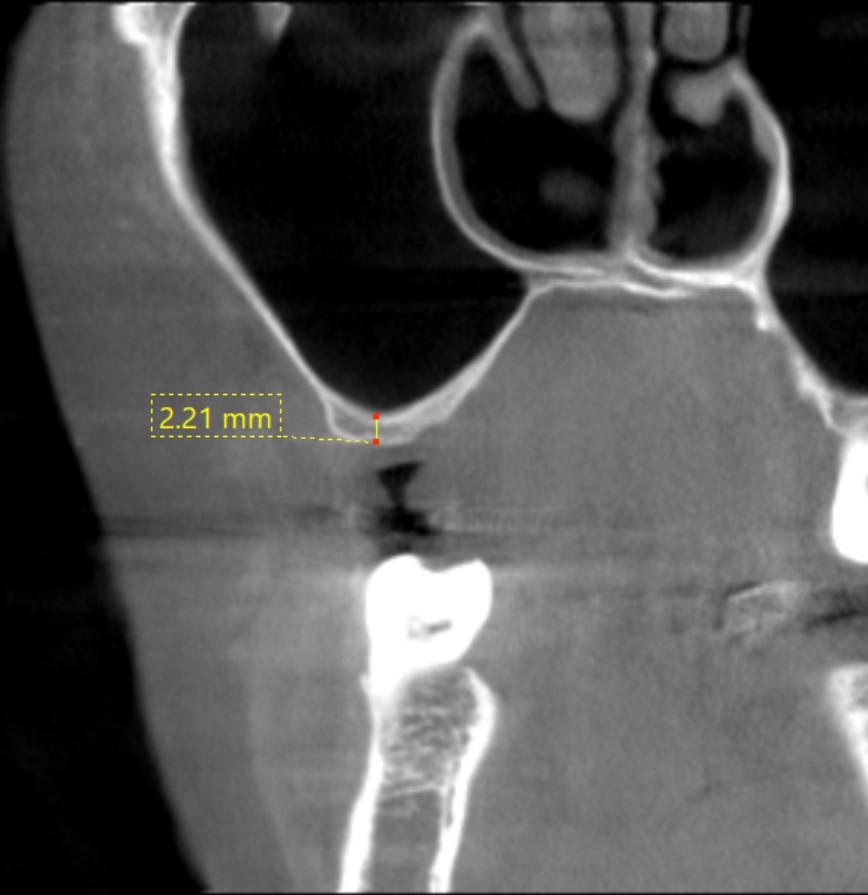

初診時

術後